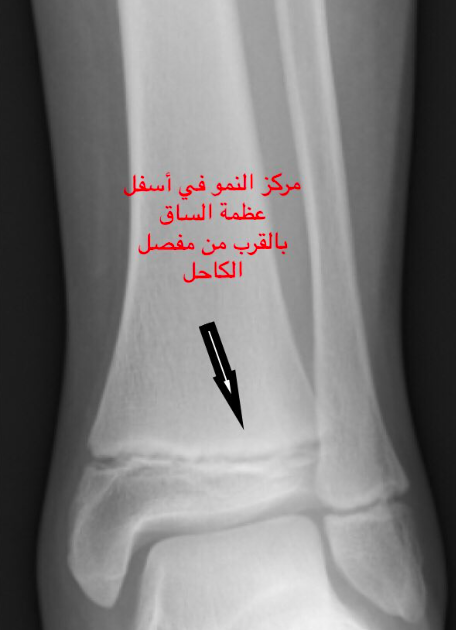

كسور الأطفال